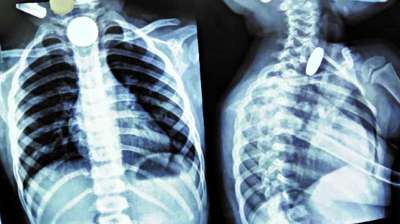

खिलौना नहीं सिक्का था! बच्चे ने निगले 5-10 रुपये के सिक्के, डॉक्टरों ने ऑपरेशन कर निकाले

24 Jul, 2025 04:09 PM IST | SATTASUDHAR.IN

दिल्ली : दिल्ली के एक सरकारी अस्पताल के डॉक्टरों ने 12 वर्षीय बच्चे की जान बचाई है। बच्चे ने पांच और दस रुपये के तीन सिक्के निगल लिए थे। सिक्के...